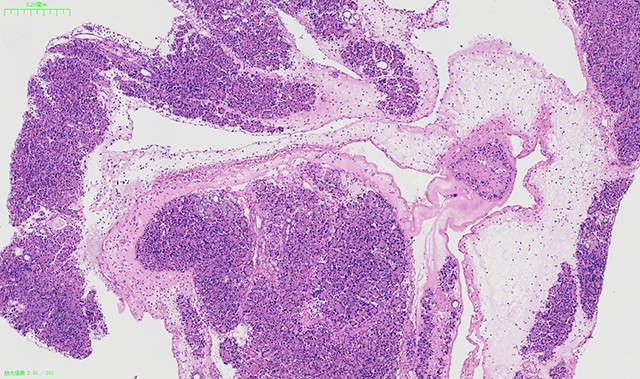

在病理学领域,HE染色(Hematoxylin and Eosin Staining)作为一种经典的染色方法,被广泛应用于组织样本的观察和分析。HE染色不仅为病理医生提供了直观的细胞形态和结构信息,还为疾病的诊断和治疗提供了重要的依据。

HE染色在诊断疾病方面起着至关重要的作用。通过观察染色后的组织样本,病理医生可以判断出病变的性质、范围以及与周围组织的关系。例如,在肿瘤的诊断中,HE染色可以帮助医生判断肿瘤的类型、分化程度以及是否侵犯周围组织……这些信息对于制定治疗方案和评估预后具有重要意义。